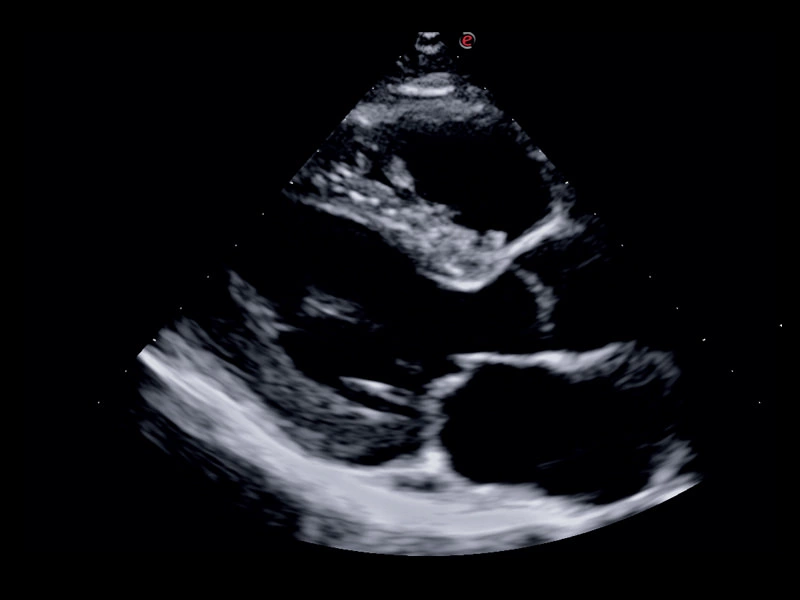

MyLab™Sigma - High definition B-mode cardiac imaging

MyLab™Sigma - High definition B-mode cardiac imaging

Q7 - CV Cardio B-mode

Q7 - CV Cardio B-mode

Q7 - CV Cardio B Mode 2

Q7 - CV Cardio B Mode 2